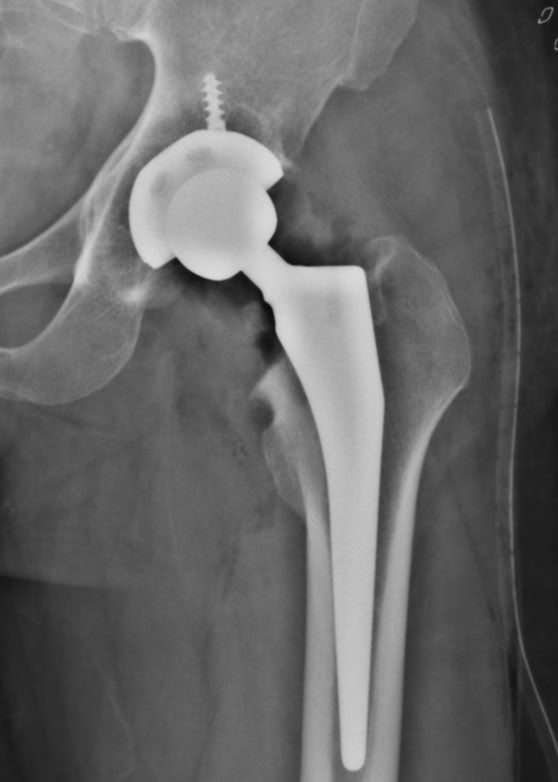

Pase de visita para preparar el parte de los quirófanos del lunes . Teníamos dos pacientes para prótesis de cadera, algunas fracturas abiertas para fijadores  y algunas cosas más que fueron  programadas. Y el lunes  después de el rezo en la capilla y la presentación de los miembros de la expedición, comenzamos el trabajo en quirófano y en consultas